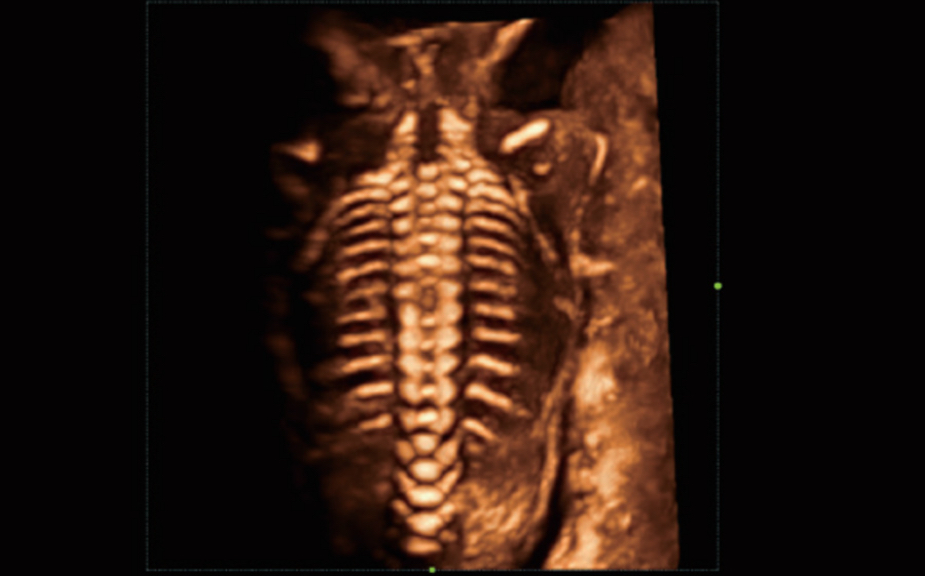

El sistema Nuewa I9, dise?ado exclusivamente para la atenciĂłn mĂ©dica neonatal y de mujeres, brinda una experiencia innovadora integral. Estas innovaciones se desarrollan sobre la base de un conocimiento profundo de situaciones clĂnicas complejas para proporcionar respuestas precisas y oportunas, una gran eficiencia y una experiencia de usuario extraordinaria.

SoluciĂłn completa con tecnologĂa de ZST +

La plataforma ZST+?es una innovaciĂłn extraordinaria que representa toda una evoluciĂłn en el ĂĄmbito de la ecografĂa. Transforma las mĂ©tricas ecogrĂĄficas de la formaciĂłn de haces convencional al procesamiento basado en datos de canal. Supera la limitaciĂłn tradicional de tener que equilibrar entre resoluciĂłn espacial, resoluciĂłn temporal y uniformidad del tejido, con lo que ofrece una calidad de imagen excepcional para soluciones de producciĂłn de imĂĄgenes infinitas con mejoras continuas.